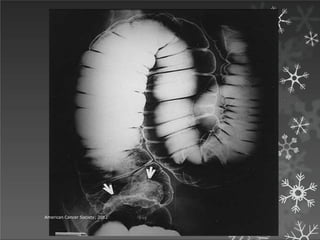

Enema de bario de doble contraste cada 5 años.*(ca y

polipos mayores a un cm)

Enema baritado